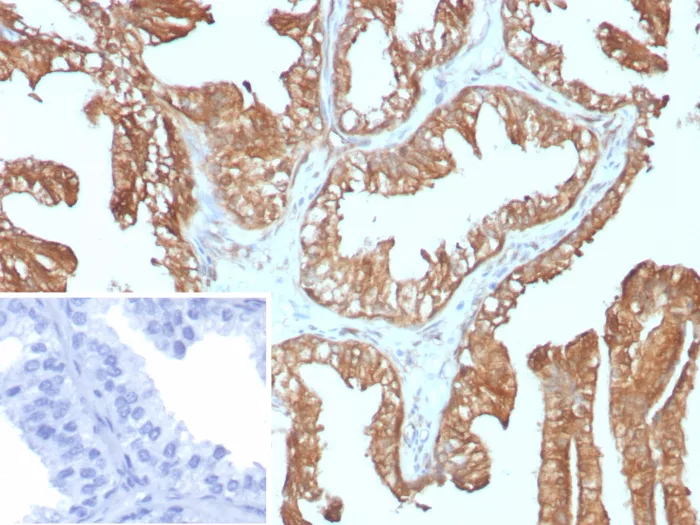

Formalin-fixed, paraffin-embedded human prostate carcinoma stained with 14-3-3E Recombinant Mouse Monoclonal Antibody (rYWHAE/8860). HIER: Tris/EDTA, pH9.0, 45min. 2°C: HRP-polymer, 30min. DAB, 5min.